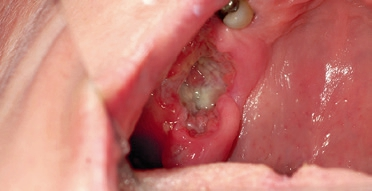

Die klinische Diagnose der Leukoplakie muss feingeweblich (histologisch) gesichert werden. Hierzu werden die weißlich erscheinenden Veränderungen nach Entnahme mit dem Mikroskop untersucht. Histologisch stellt man eine unterschiedlich stark ausgeprägte Hyperkeratose fest, welche die Läsion klinisch in der Mundschleimhaut weiß erscheinen lässt [19]. Zusätzlich können sich Dysplasien in unterschiedlicher Ausprägung bis hin zum Carcinoma in situ zeigen [20]. Abhängig von diesem Befund wird die Läsion je nach Schweregrad eingeteilt. Es werden geringe, mäßige oder schwere Epitheldysplasien unterschieden. Die schwere Form der Epitheldysplasie entspricht dem frühen Carcinoma in situ [21] (Abb. 3).

Ohne eine histopathologische Untersuchung ist eine Differenzierung häufig nicht möglich. Dies zeigt der in Abbildung 3 dargestellte klinische Fall. Diese Schleimhautveränderung stellte sich klinisch als eine homogene Leukoplakie dar und entpuppte sich nach histologischer Untersuchung als ein Plattenepithelkarzinom der Mundhöhle im frühen Stadium (Carcinoma in situ).